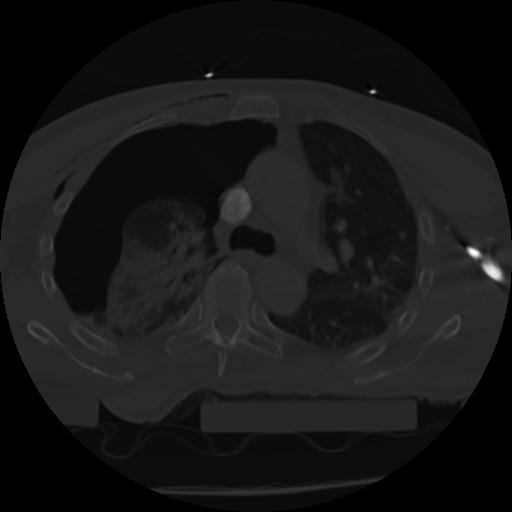

21 ANGIO,CE,Axial,3.0,ANGIO,,